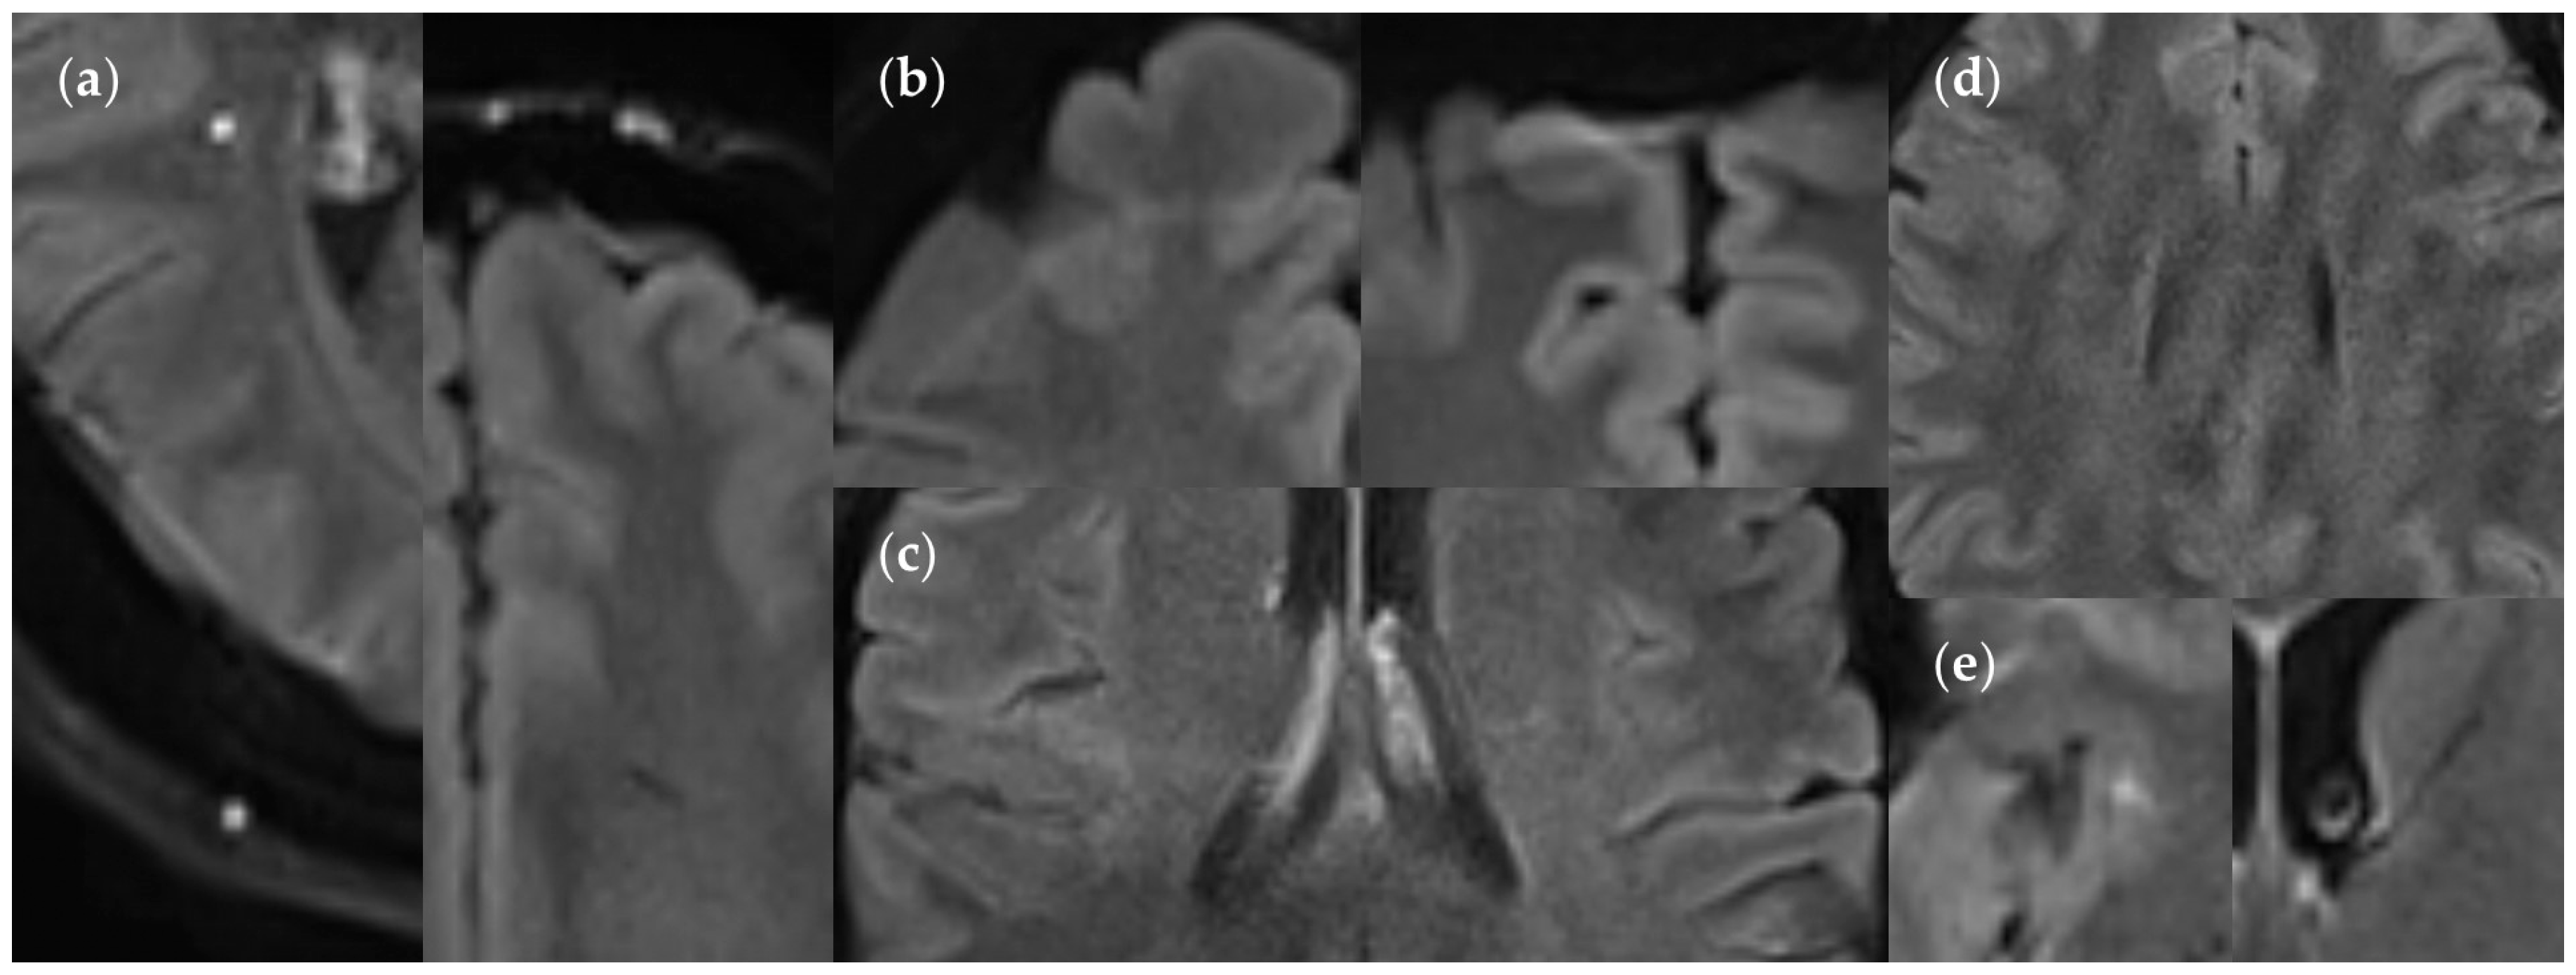

3.3.3. Positional Dependence of SNR and CNR in FLAIRUF

4.3. Limitations of the FLAIRUF Images

4.4. Considerations on Ratings for Lesion Conspicuity in FLAIRUF

4.5. Outcomes Correlated with Technical Features